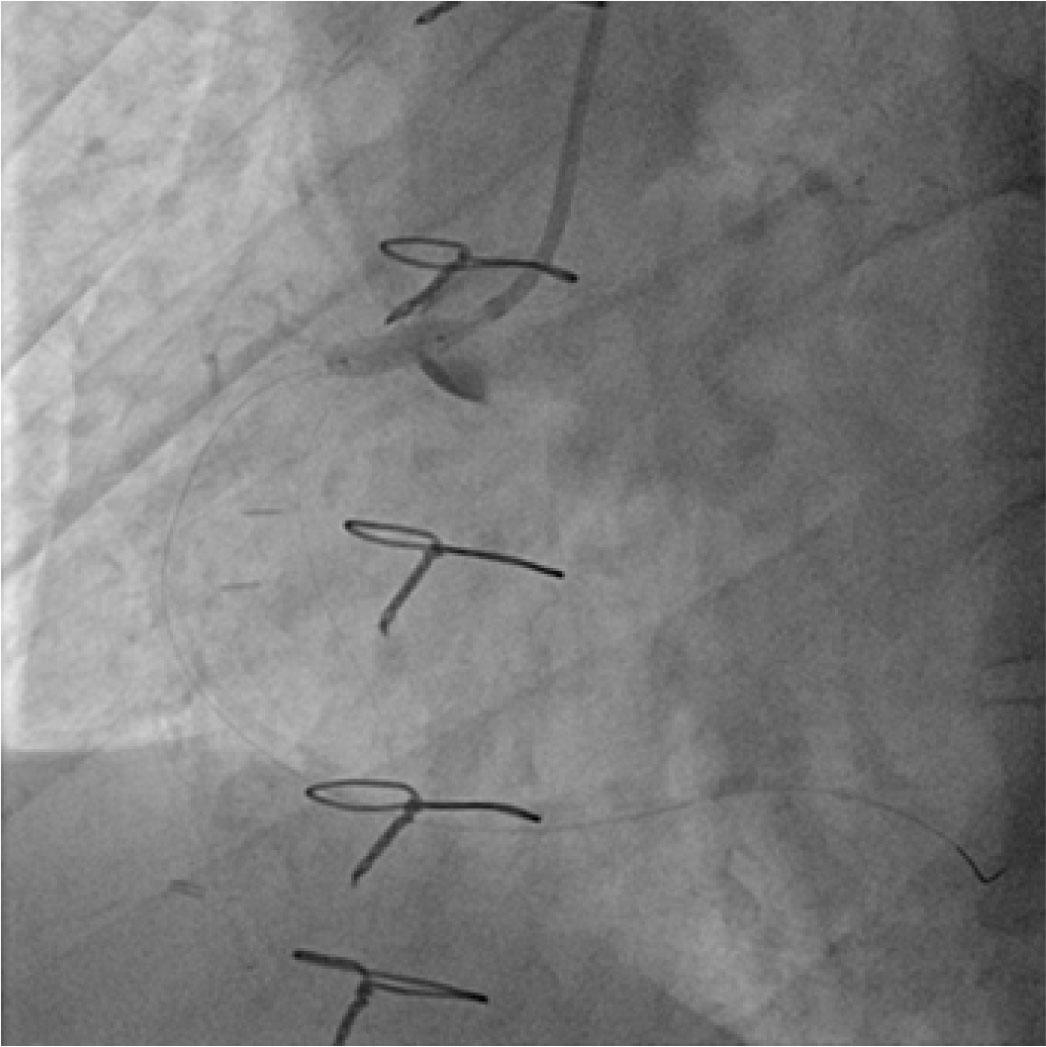

He was taken immediately to the catheterization laboratory. Transfemoral diagnostic coronary angiography using CORDIS DIAGNOSTIC 6F JL4 (IndiaMART) and JR4 (Oscor’s Angios) catheters revealed patency of LAD graft, significant stenosis of the proximal left circumflex coronary artery (LCX) followed by chronic total occlusion of the distal segment, and complete thrombotic occlusion of the proximal right coronary artery (RCA) with retrograde filling of distal RCA through collaterals from LAD (Figure 1). Consequently, we proceeded to PCI to the proximal RCA. We used a CORDIS DIAGNOSTIC 6F JL4 (IndiaMART) guide catheter to engage the RCA, and an attempt was made to cross the culprit lesion with a 0.014” PT2 moderate support guidewire (Boston Scientific). The control contrast injection revealed a long spiral dissection of RCA (Type D according to the NHLBI classification) starting fromthe tip of the guide catheter with antegrade extension to the distal segment and evidence of thrombus in the mid-portion and slow flow. Subsequent angiogram revealed retrograde extension into the right aortic sinus of Valsalva and ascending aorta and dye retention extending more than 50 mm in the aortic wall, consistent with class III Dunning aortocoronary dissection (Figure 2).

Type D RCA dissection extending to ascending aorta, consistent with class III Dunning aorto-coronary dissection.